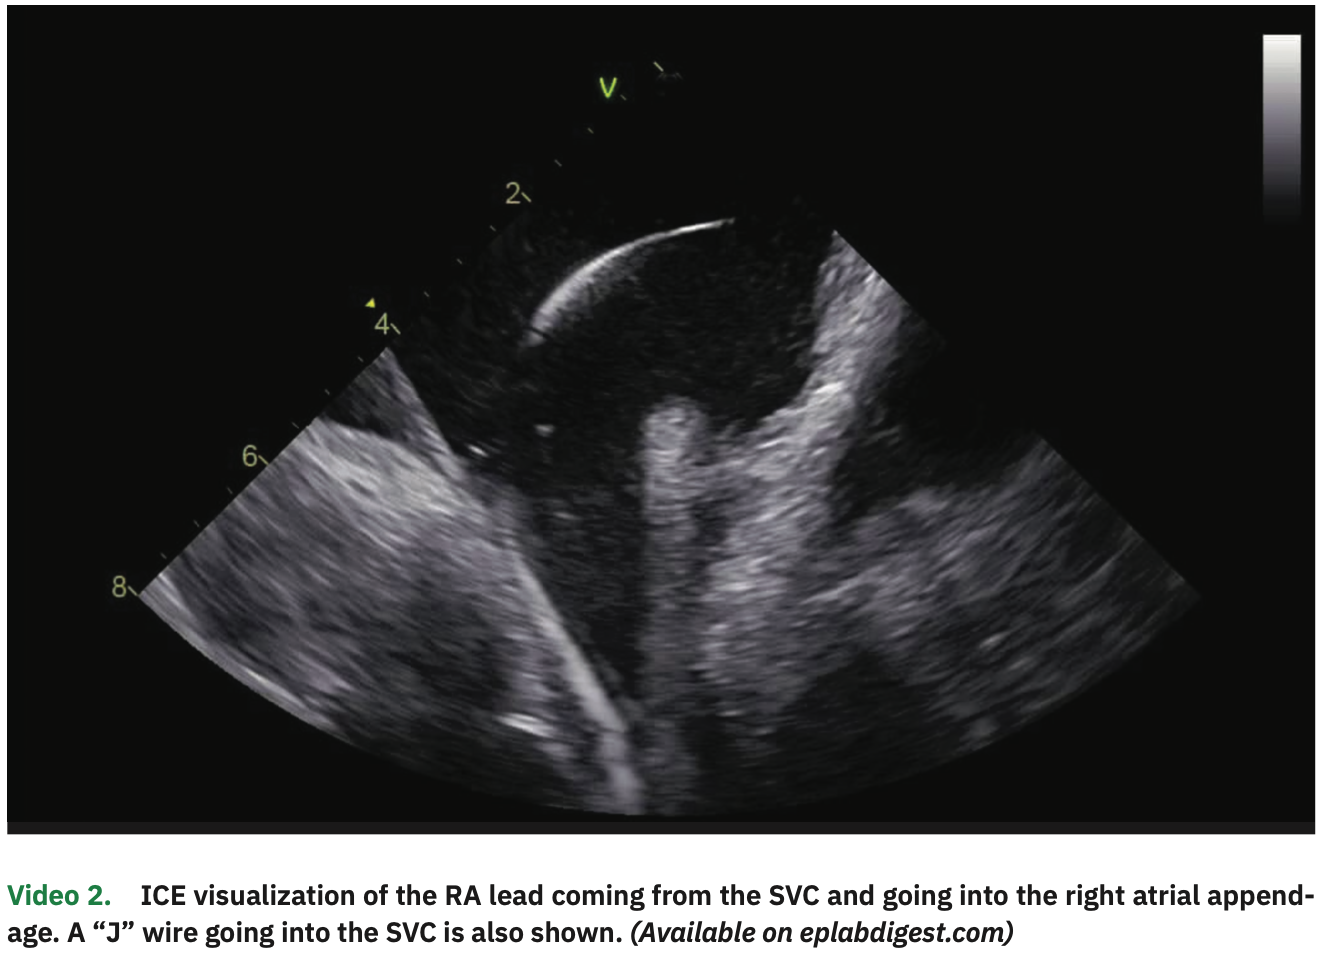

The procedure was performed under general anesthesia and on uninterrupted apixaban (last dose in the evening before the early morning procedure). The patient was in paced rhythm both in the atrial and ventricular channels. Venous access was obtained in the right and left femorals as well as in the right internal jugular vein, all guided by ultrasound. From the left femoral vein, an ICE catheter was advanced to the right atrium (RA), guided by visualization of echo-free spaces in the vascular system (Video 1). The pacemaker leads were clearly visualized in the RV septum and right atrial appendage (Figure 1 and Video 2). A multipolar esophageal catheter was placed and its position guided by ICE visualization.

In particular, ICE visualization is key in every step of the way. We are even promoting a new hashtag on social media for this (#ICEeyes), since ICE is our “eyes” to see what we are doing. With thorough ICE scanning, all the steps can be adequately monitored, even as catheters come out of the sheath tip (making sure it does not force on the atrial wall). There is no blind step using this approach, even when advancing catheters or wires in the venous system to the heart. CS visualization and cannulation are better than with fluoroscopy. Transseptal punctures are also undoubtedly best visualized on ICE. A short learning curve is required to become comfortable and proficient in ICE manipulation; however, we feel that ICE definitively provides better and more detailed information than fluoroscopy.